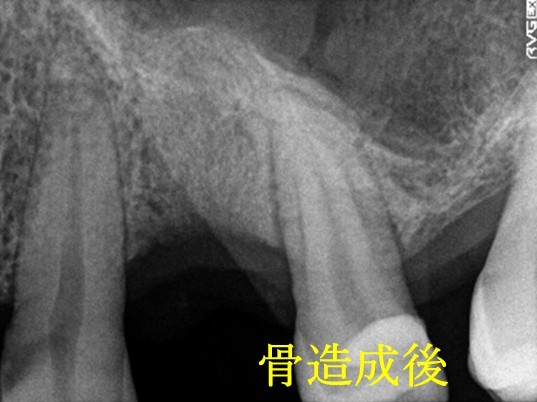

歯周病が進行し、保存することができず抜歯しました。大きく骨が欠損していましたので、骨造成後インプラントを埋入しました。

所感

抜歯後、ブリッジ、1本義歯の選択肢もありましたが、インプラントを選択されました。治療後「初めての治療でしたが良かったです。今後もし歯を失うことがあったら、インプラントをしようと思いました。」という感想をいただきました。今回もX-Guideを使った埋入で、安心安全に行うことできました。

骨造成:¥55,000(税込)

インプラント1本:¥363,000(税込)

合計:¥418,000(税込)